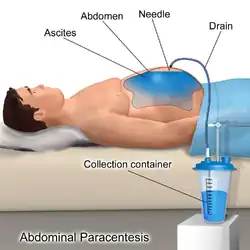

- Aszitespunktion (Parazentese)

Mechanische Entlastung

Schwere, therapierefraktäre Verläufe können zusätzlich mit Parazentese, also der Abpunktion der Flüssigkeit, mit gleichzeitiger Albumingabe und anschließender Rezidivprophylaxe mit Diuretika (Medikamente zur Steigerung der Nierenausscheidung) behandelt werden. Bei dieser Methode wird der Erguss durch die Bauchdecke punktiert und abgelassen. Da sich der Aszites meist schnell wieder bildet, muss diese Methode zwangsläufig wiederholt werden. Dies kann vom Arzt zwar ambulant durchgeführt werden, Nachteile sind jedoch dabei, dass bei jeder Wiederholung das Risiko von Blutungen, von bakteriellen Infektionen des Bauchraums und von Verletzungen vorhanden ist.